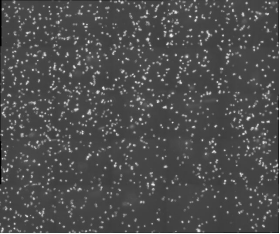

北京眼科研究所致力于探索眼科疾病的發(fā)病機(jī)制和治療方法,其中免疫學(xué)研究是其重要方向之一。在一項(xiàng)關(guān)于小鼠巨噬細(xì)胞的研究中,科研人員需要對(duì)細(xì)胞進(jìn)行長(zhǎng)時(shí)間的動(dòng)態(tài)監(jiān)測(cè),以觀察其在免疫反應(yīng)中的行為變化。然而,傳統(tǒng)的顯微鏡在長(zhǎng)時(shí)間成像時(shí)往往面臨成像速度慢、清晰度不足以及軟件操作復(fù)雜等問題,這些問題嚴(yán)重限制了研究的進(jìn)展。

MCS31配備了10XPH和20PH高分辨率物鏡,能夠提供清晰、細(xì)膩的細(xì)胞圖像,滿足基本的細(xì)胞成像需求。